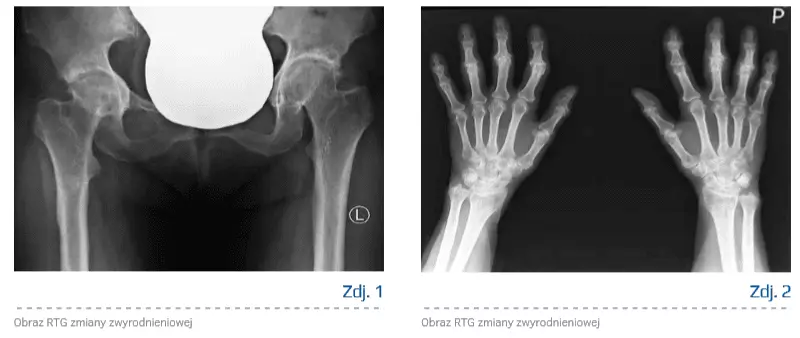

Choroba zwyrodnieniowa

Choroba zwyrodnieniowa stawów dotyka coraz większą część społeczeństwa. Wydłużający się czas życia i mała ilość ruchu stwarzają sprzyjające okoliczności dla rozwoju choroby. Chrząstka stawowa stanowiąca wieńczącą kość strukturę narażona jest na nacisk, wstrząsy oraz ciągły ruch ślizgowy trących o siebie powierzchni stawowych. Zaburzenia w jej prawidłowej strukturze doprowadzają do rozwoju zmian zwyrodnieniowych. Strukturę tę stanowią chondrocyty oraz macierz, w której są zawieszone (90% masy). Składnikami budulcowymi macierzy są głównie woda (powyżej 65%), białka i lipidy, a spośród białek należy wymienić przede wszystkim kolagen oraz proteoglikany.

Proces zapalny powoduje destrukcję chrząstki stawowej i prowadzi do utraty stabilności chrząstki, jej przebudowy i włóknienia. W dalszym etapie dochodzi do sklerotyzacji kości w okolicy podchrzęstnej. Istotą zmian zwyrodnieniowych jest to, że proces nie toczy się tylko w obrębie chrząstki stawowej, ale obejmuje cały staw (podchrzęstna warstwa kości, błona maziowa, torebka stawowa itd.).

W przypadku reumatoidalnego zapalenia stawów uzyskano ewidentne efekty zmniejszenia procesu zapalnego, jednak wobec wątpliwości, co do etiologii choroby zwyrodnieniowej stawów – czy proces zapalny występuje pierwotnie, czy też wtórnie – stosowanie preparatów niezdenaturowanego kolagenu typu II pozostawało przedmiotem dyskusji. W badaniach stwierdzono, że w przebiegu choroby zwyrodnieniowej przez błonę maziową są produkowane cytokiny, czynniki wzrostowe i prostaglandyny, co doprowadza do produkcji metaloproteinaz w komórkach macierzy chrząstki, co w dalszej kolejności skutkuje stopniową degradacją chrząstki w mechanizmie zapalnym [8]. Produkcja kolagenazy przez zmienioną zapalnie błonę maziową i aktywowane chondrocyty ma charakter samonapędzającego się mechanizmu wzmagającego autodegradację chrząstki i rozwoju choroby zwyrodnieniowej [9–11]. Wobec powyższego oprócz mechanizmu biomechanicznego, osteoporotycznego i metabolicznego należy wskazać także mechanizm zapalny i w zależności od etiologii stosować różną terapię – w przypadku pacjentów z zaburzeniami mechanicznymi należy pamiętać o leczeniu odciążającym, zmieniającym mechanikę stawu (redukcja masy ciała, odciążanie, wiskosuplementacja, leczenie operacyjne), w przypadku pacjentów ze schorzeniem o podłożu osteoporotycznym odpowiednia będzie farmakoterapia.